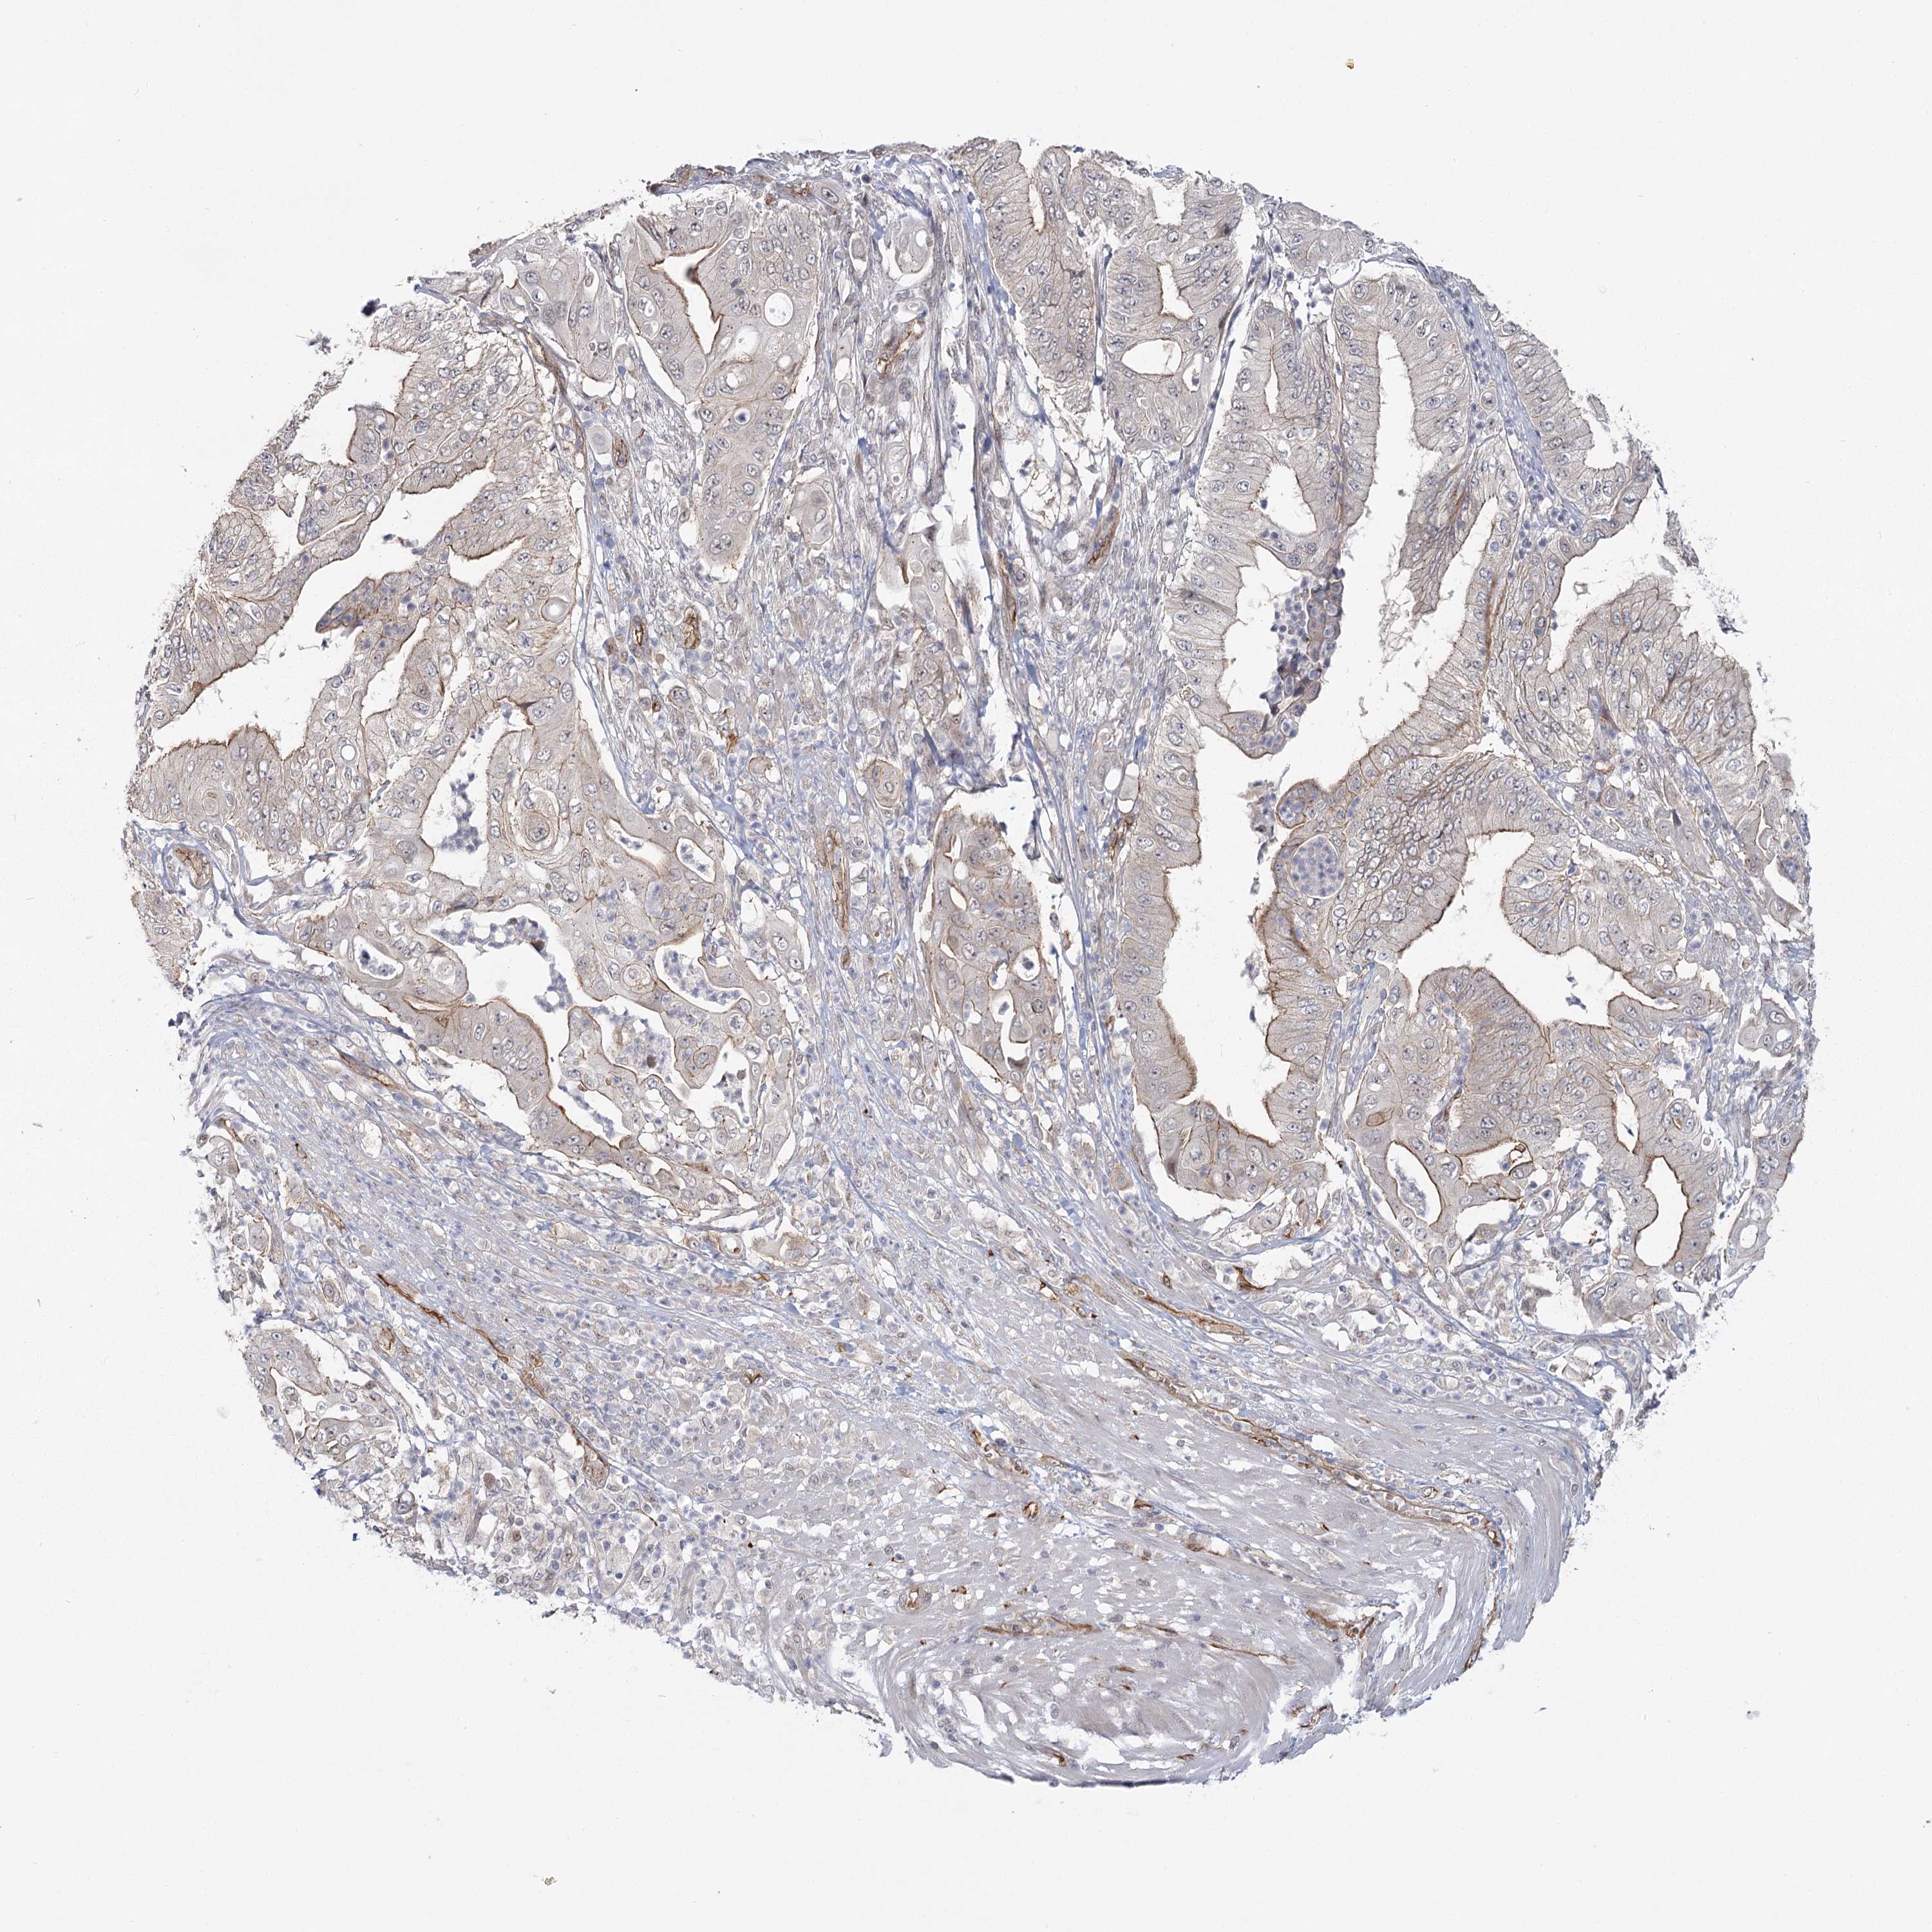

PANCREATIC CANCER - Protein expressioni

A mouse-over function shows sample information and annotation data. Click on an image to view it in a full screen mode. Samples can be filtered based on level of antibody staining by selecting one or several of the following categories: high, medium, low and not detected. The assay and annotation is described here.

Note that samples used for immunohistochemistry by the Human Protein Atlas do not correspond to samples in the TCGA dataset.

Antibody stainingi

Antibody staining in the annotated cell types in the current human tissue is reported as not detected, low, medium, or high, based on conventional immunohistochemistry profiling in selected tissues. This score is based on the combination of the staining intensity and fraction of stained cells.

Each image is clickable and will lead to virtual microscopy that enables deeper exploration of all samples and also displays staining intensity scores, fraction scores and subcellular localization as well as patient and tissue information for each sample.

Antibody HPA036194

Staining

High

Medium

Low

Not detected

Intensity

Strong

Moderate

Weak

Negative

Quantity

>75%

75%-25%

<25%

None

Location

Nuclear

Cytoplasmic/membranous

Cytoplasmic/membranous,nuclear

Adenocarcinoma, NOS